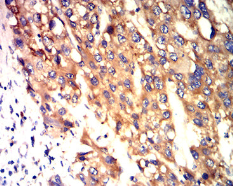

CD321 Mouse Monoclonal antibody[3B2B3]

IHC    1/200 - 1/1000